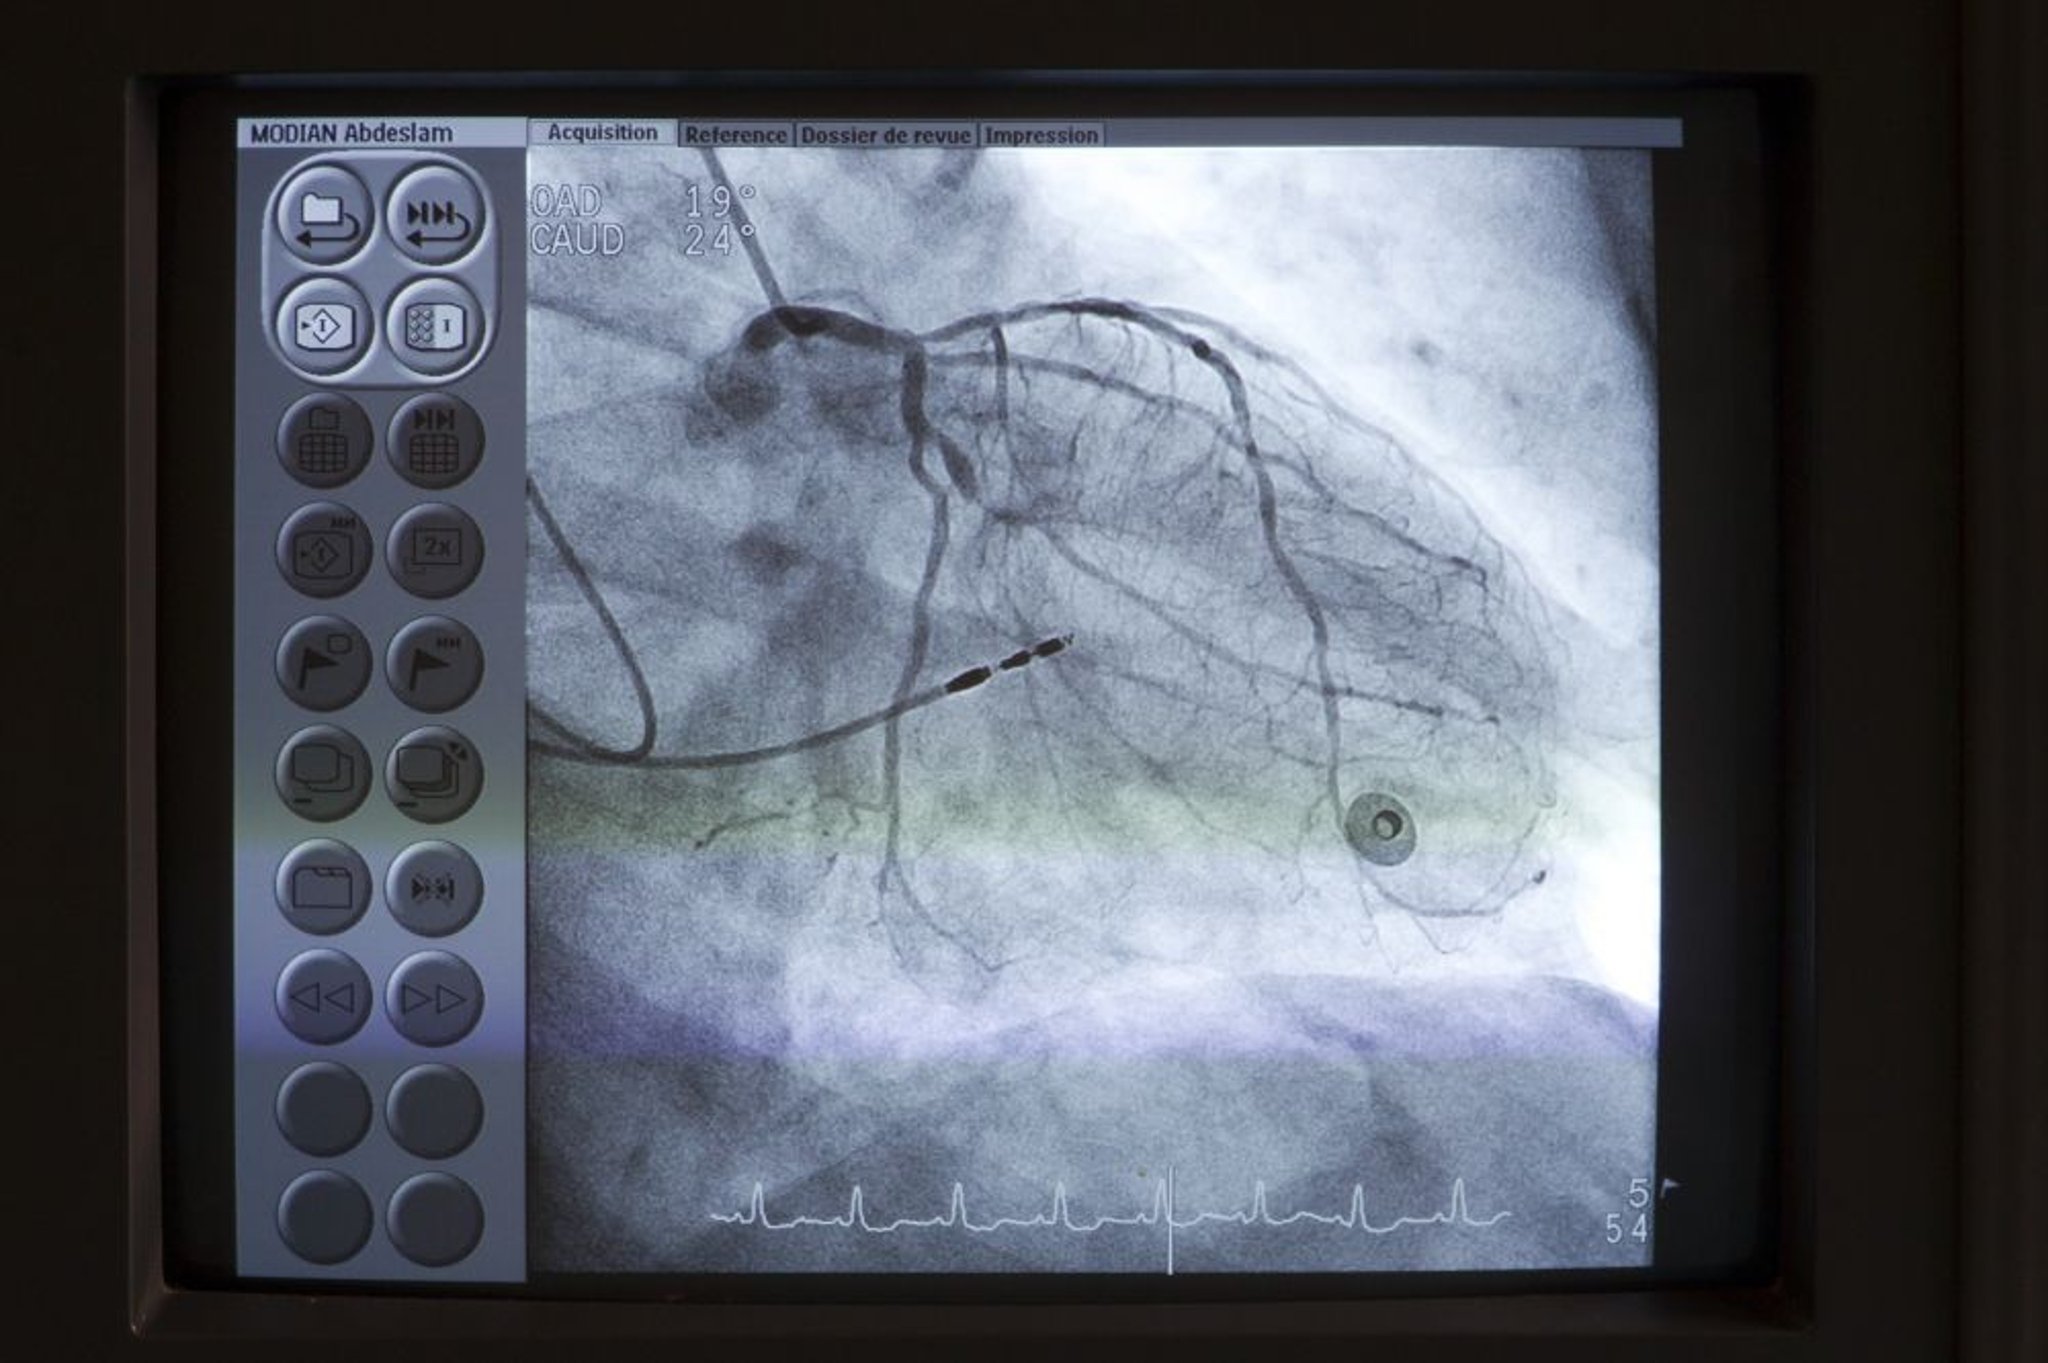

Injection of radiopaque contrast agent into coronary or pulmonary arteries, the aorta, and cardiac chambers is useful in certain circumstances. Digital subtraction angiography is used for nonmoving arteries and for chamber cineangiography.

Coronary angiography via left heart catheterization is used to evaluate coronary artery anatomy in various clinical situations, as in patients with suspected coronary atherosclerotic or congenital disease, valvular disorders before valvular replacement, or unexplained heart failure.

Coronary angiography shows the presence and degree of stenosis but not the functional significance of the lesion (ie, how much blood flows across the stenosis) or whether a specific lesion is likely to be the cause of symptoms.

Extremely thin guidewires with pressure sensors or Doppler flow sensors are available. Data from these sensors can be used to estimate coronary artery blood flow, which is expressed as fractional flow reserve (FFR). FFR is the ratio of maximal flow through the stenotic area to normal maximal flow obtained during hyperemia (most commonly with adenosine); an FFR of < 0.75 to 0.8 is considered abnormal. Newer techniques of measuring coronary blood flow, including instantaneous wave-free ratio (iFR) and diastolic hyperemia-free ratio (DFR), have been developed. These techniques have the advantage of not requiring hyperemia. Both iFR and DFR measure gradients across a stenosis during a period in diastole; an iFR or DFR of ≤ 0.89 is considered abnormal (1, 2).

These flow estimates correlate well with the need for intervention and long-term outcome; patients with lesions with FFR > 0.8, iFR > 0.89, or DFR > 0.89 do not seem to benefit from placement of a stent. These flow measurements are most useful with intermediate lesions (40 to 70% stenosis) and with multiple lesions (to identify those that are clinically most significant).

Miniature ultrasound transducers on the end of coronary artery catheters can produce images of coronary vessel lumina and walls and delineate blood flow. Intravascular ultrasonography is being increasingly used at the same time as coronary angiography in several clinical situations, including to guide optimal stent placement during percutaneous coronary intervention, detect cardiac allograft vasculopathy after heart transplantation, and identify coronary artery dissections.